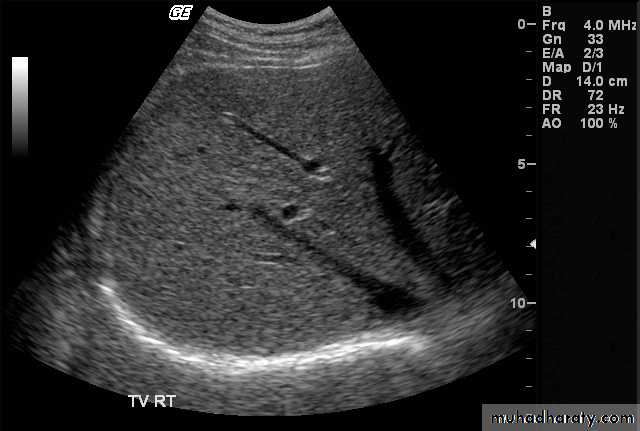

Focal masses ultrasound